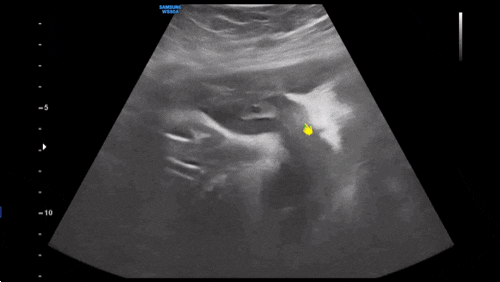

?36주차 증상? 1) 그냥 날 것의 태동 발이 어딘지 손이 어딘지 뭘 하는지 다 알수 있음..밥 먹으면 ...